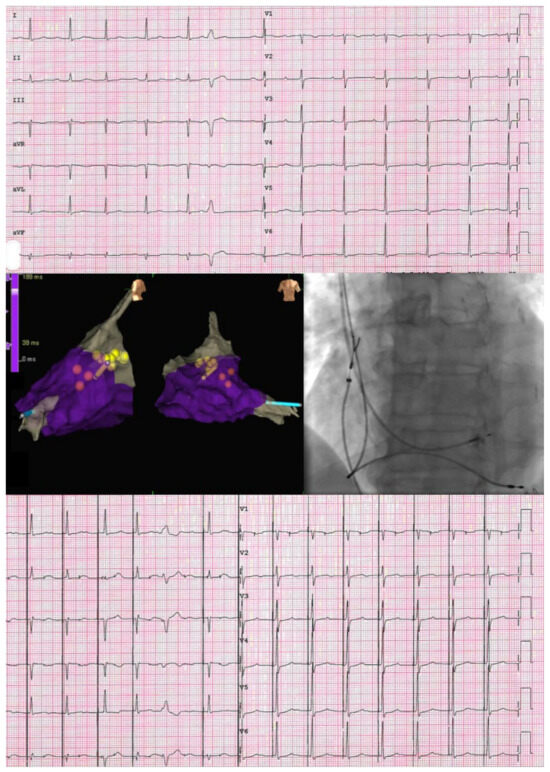

ECG and SVA Myocardial Work